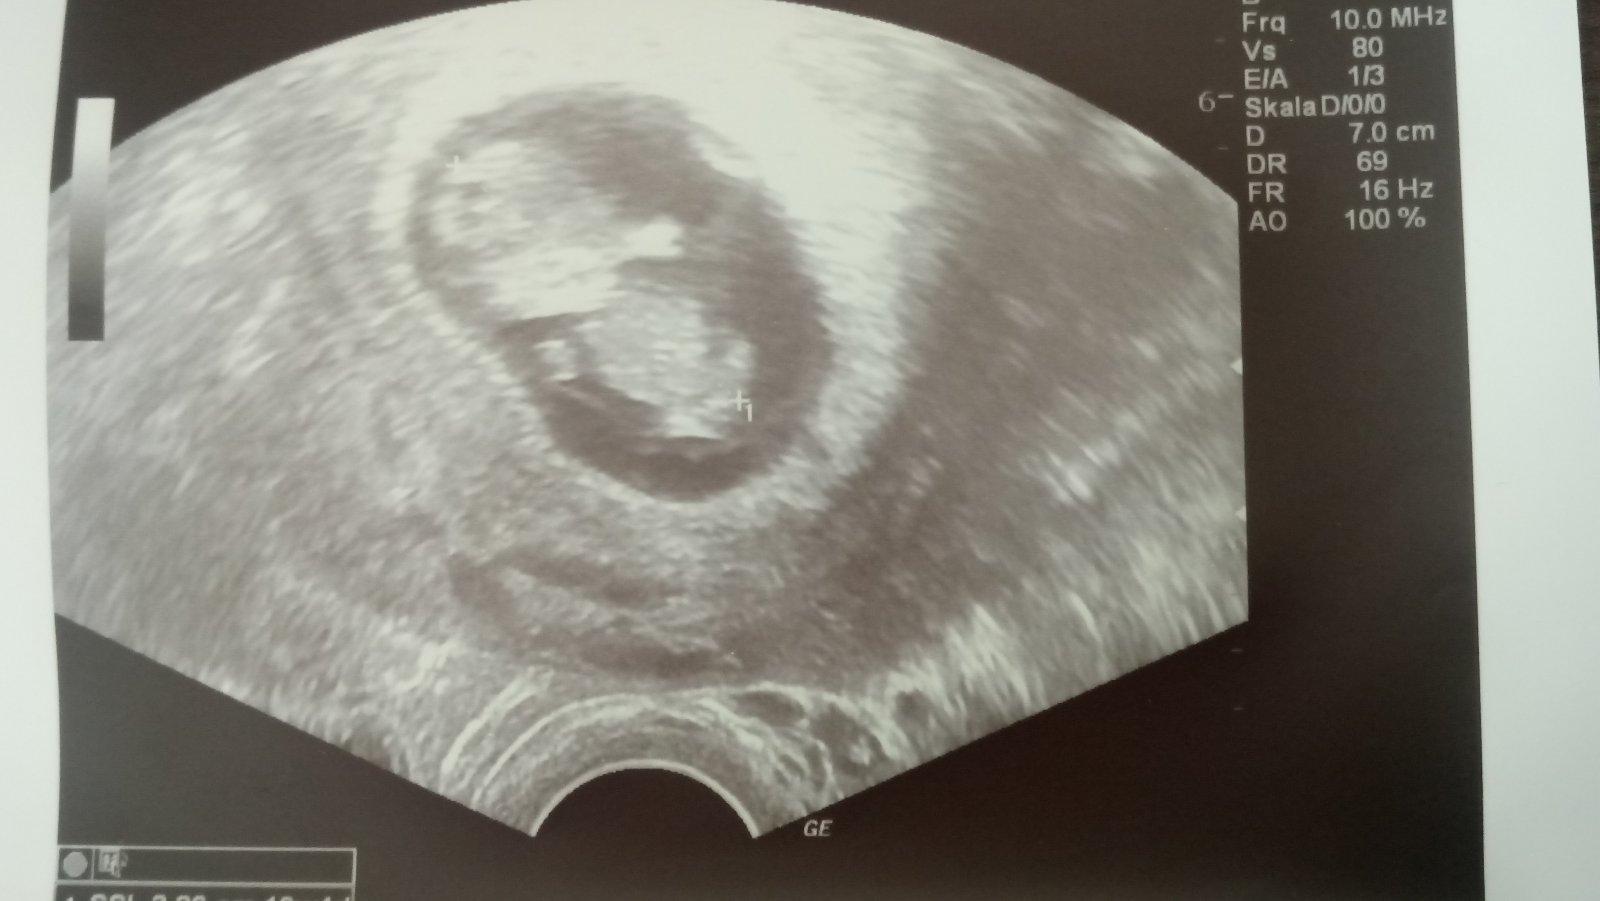

@ka_rohli_na Ideálně tak na 8tt. Abys to měla už i se srdíčkem. On Ti sice dr. řekne i dřív, že tam zárodek je, ale dokud není srdeční akce, je Ti to k ničemu a zbytečný stres, jestli příště bude. Já jsem u prvního těh. šla až v 9tt a ok a u druhého už 5+něco a srdeční akce nebyla. Tak mě objednala až na 10tt a byla to teda šíleně dlouhá doba. Naštěstí bylo vše v pořádku 🙂